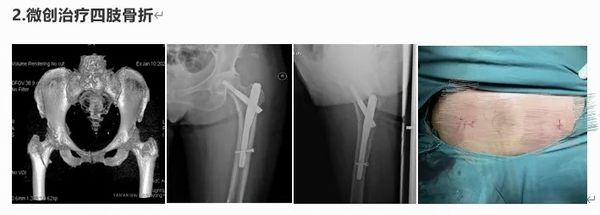

擅長四肢創(chuàng)傷骨折的微創(chuàng)修復,胸腰椎骨折復位內固定,髖關節(jié)置換術、斷指(肢)再植,拇手指再造及四肢軟組織缺損的顯微外科。